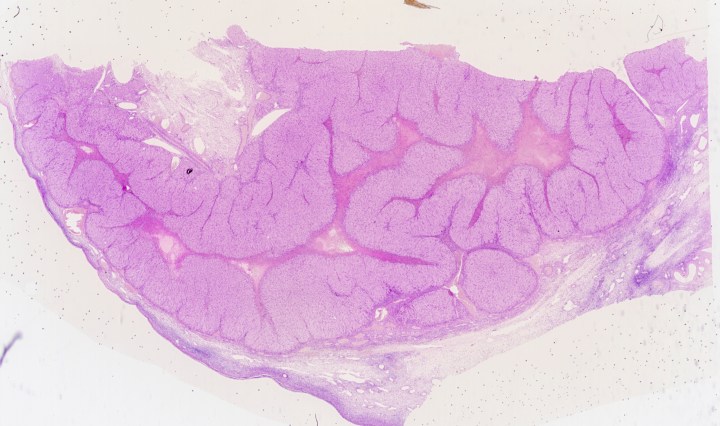

Large Intestine

The large intestine is the penultimate portion of the digestive tract, between the small intestine and the rectum. The muscularis externa layer continues to separate into the circular and the longitudinal layer, with the exception that the longitudinal layer forming … Continue reading Large Intestine